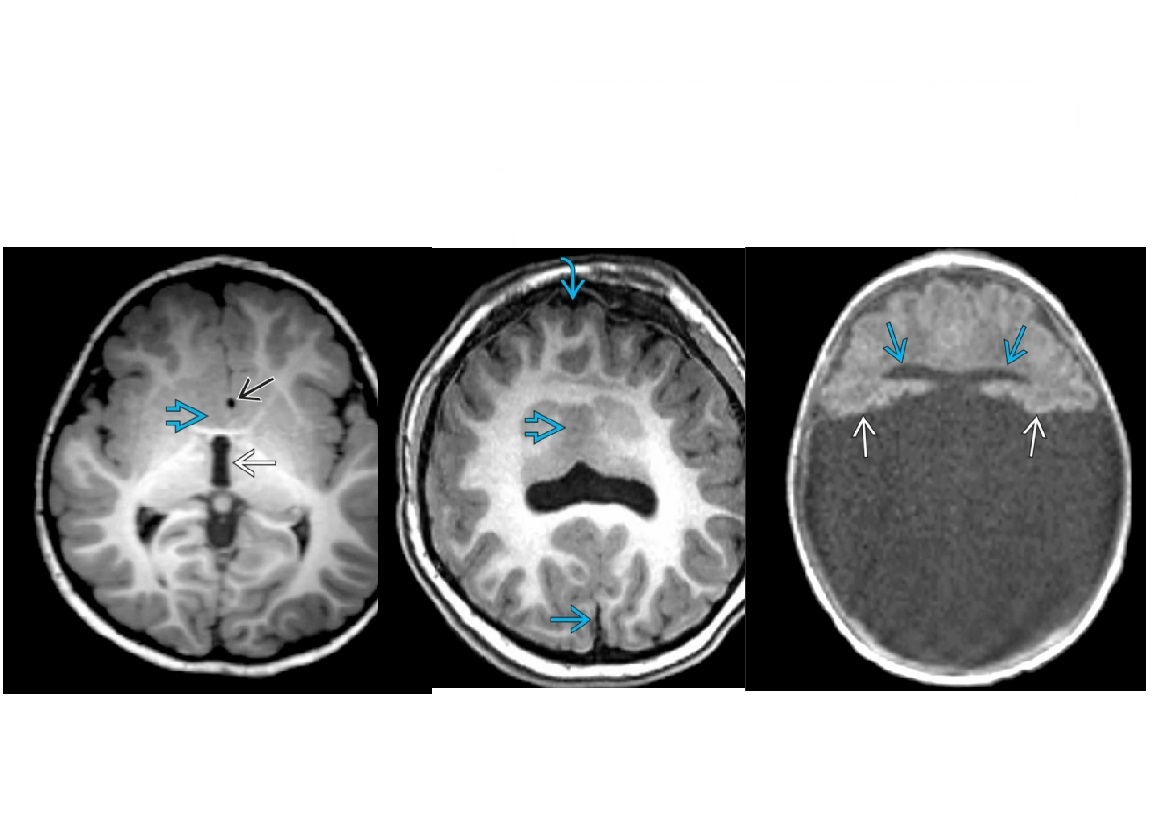

Monoventricle, thalami and basal ganglia are fused?

A

Alobar Holoprosencephaly

Addition: Most severe form.

**No falx or corpus callosum

Complete absence of cleavage with “pancake” of anterior cerebral tissue, crescent-shaped anterior monoventricle communicating with large dorsal cyst,** fused thalami**

Lobar Holoprosencephaly

Mildest from of holoprosencephaly

Cleavage is apparently back to front (opposite the corpus callosum ) so posterior fossa is normal in mildest form

Interhemispheric fissure & falx are mostly formed with partial nonseparation of frontal lobes